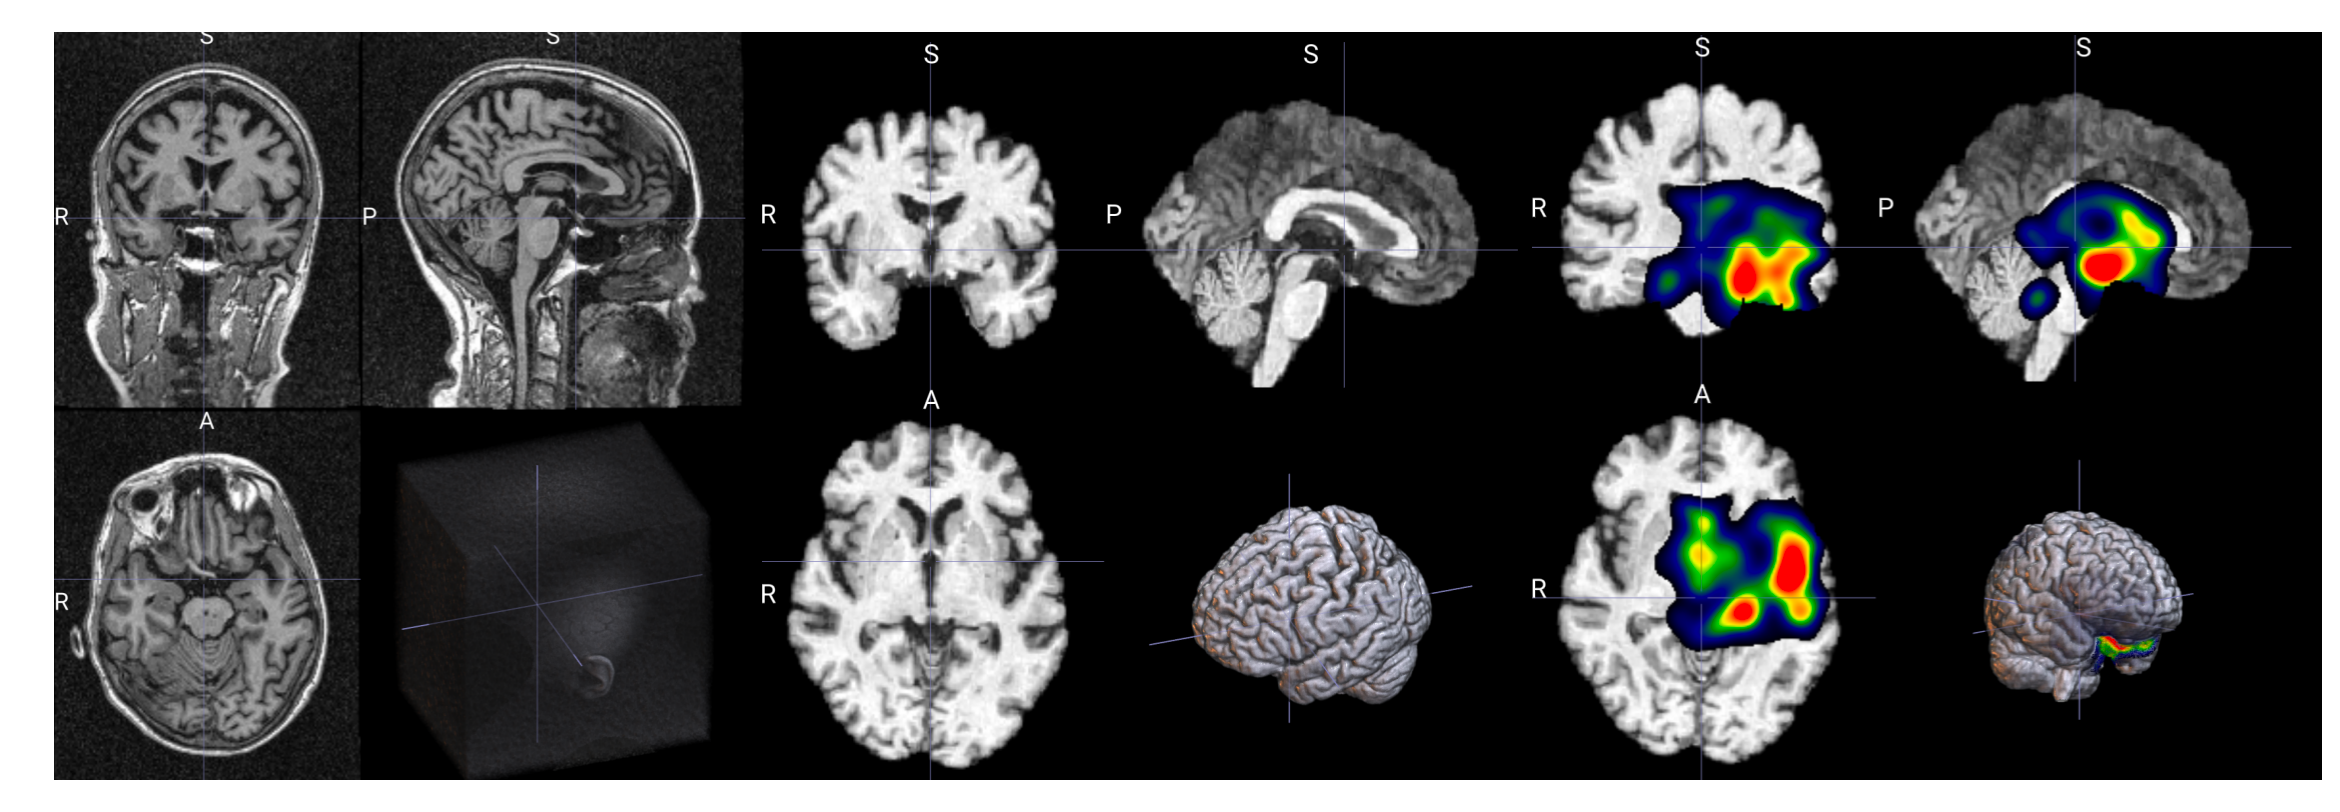

该脚本完成以下工作:

- 加载 3D NIfTI 医学影像(如 MRI)

- 使用 MONAI 进行预处理(需调整为训练所用的预处理)

- 使用训练好的模型进行推理

- 通过 SmoothGrad 生成梯度注意力图

- 对 heatmap 进行后处理(平滑 + mask + 归一化)

- 输出 .nii.gz 热力图文件及相关信息

输出示例